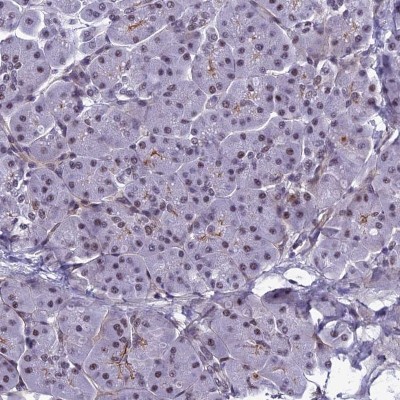

- Experimental details

- Immunohistochemistry-Paraffin: RSRC1 Antibody [NBP1-90756] - Staining of human pancreas shows low expression as expected.